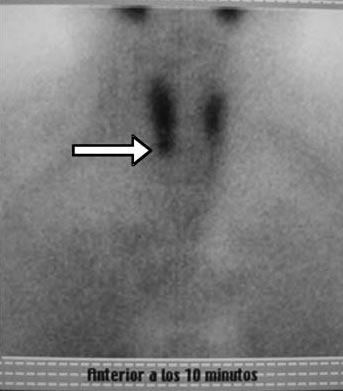

Dos meses después de la PAF se efectúa cintigrama paratiroideo con 99mTc-MIBI, que señala, en las placas tempranas (+10 min), un área de hipercaptación del isótopo a nivel del polo inferior derecho, coincidente con la localización ecográfica del nódulo biopsiado, señal que desaparece en las placas tardías (Figuras 3a y 3b).

La hiperplasia paratiroidea que normalmente compromete a las cuatro glándulas, no es necesariamente equivalente para cada una de ellas, pudiendo una o dos comandar el crecimiento, como creemos que sucedió en nuestro caso en que la ecografía y la cintigrafía paratiroidea lo demuestran.